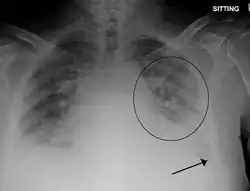

Obrzęk płuc – stan chorobowy, w trakcie którego w pęcherzykach płucnych zamiast powietrza zaczyna gromadzić się płyn przesiękowy, który utrudnia wymianę gazową w płucach.

Do takiej sytuacji dochodzi najczęściej w przebiegu niewydolności krążenia (lewokomorowej niewydolności serca), ale także w przypadku utrudnienia odpływu krwi z płuc (w przypadku wad serca), jak również w przypadku zaburzeń toksycznych lub przemiany materii, w trakcie których dochodzi do uszkodzenia pęcherzyków płucnych (mocznica, zespół nerczycowy).

Najczęstszą jego przyczyną jest skrajnie ciężka zastoinowa niewydolność krążenia, w trakcie której, zgodnie z gradientem ciśnienia, dochodzi do przesiękania płynów z naczyń krwionośnych do światła pęcherzyków płucnych.